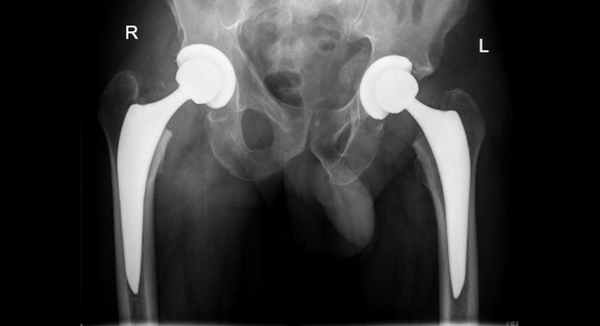

- Эндопротезирование. Заключается в полной замене поврежденной части или всего тазобедренного сустава искусственным аналогом.

Как следует из таблицы 3, в большинстве случаев преобладали хорошие и удовлетворительные результаты – 86,4 %. Последними считали проявления у пациентов дегенеративного артроза с умеренным болевым синдромом при физических нагрузках и ограничение движений в тазобедренном суставе, не препятствующее ходьбе. У 12 пациентов с неудовлетворительными результатами выполнено эндопротезирование пораженного сустава в сроки до 7 лет после травмы, у 9 из них были тяжелые комбинированные переломы задней стенки, у 3 – простые. Статистическая значимость в отдаленных результатах у пациентов, леченных консервативно и оперативно, отсутствует (p > 0,5). Однако, так как консервативному лечению подвергались пациенты с переломами вертлужной впадины без смещения отломков, а оперативному – с наиболее тяжелыми повреждениями со смещением отломков и вывихом бедра, можно уверенно утверждать, что оперативное лечение позволяет получить более приемлемые результаты и уменьшить риск развития дегенеративного артроза поврежденного сустава в большинстве случаев.

Если по истечении заданного периода времени сращения не происходит, то перелом считается несрастающимся. В таких случаях выходом является полная или частичная замена сустава на имплантат. При необходимости применяется дополнительный костный материал.

После точной диагностики при помощи КТ выявляется степень смещения тазовых костей. Если смещение минимально, то применяется тракция (вытяжение) и заживление в течение реабилитационного периода. Если же смещение существенное, а также присутствует вывих, то после вправления используется скелетное вытяжение. После вытяжения делается анализ состояния сустава: при удачном совпадении осколков производится тракция и реабилитация, при оставшемся смещении решается вопрос об оперативном вмешательстве. Если перелом в данный момент времени неоперабельный, то через 4-6 месяцев проводится эндопротезирование. В случае возможности проведения операции применяются следующие методы: артротомия, репозиция, стабильная фиксация.

Неоперабельным считается многооскольчатый перелом. При этом может возникнуть некроз головки, а также деформирующий артроз сустава. Остеосинтез не рекомендован, оптимальным вариантом является замена сустава. Свободные костные частицы необходимо удалить, поскольку они вызывают боль и деформируют суставные ткани.